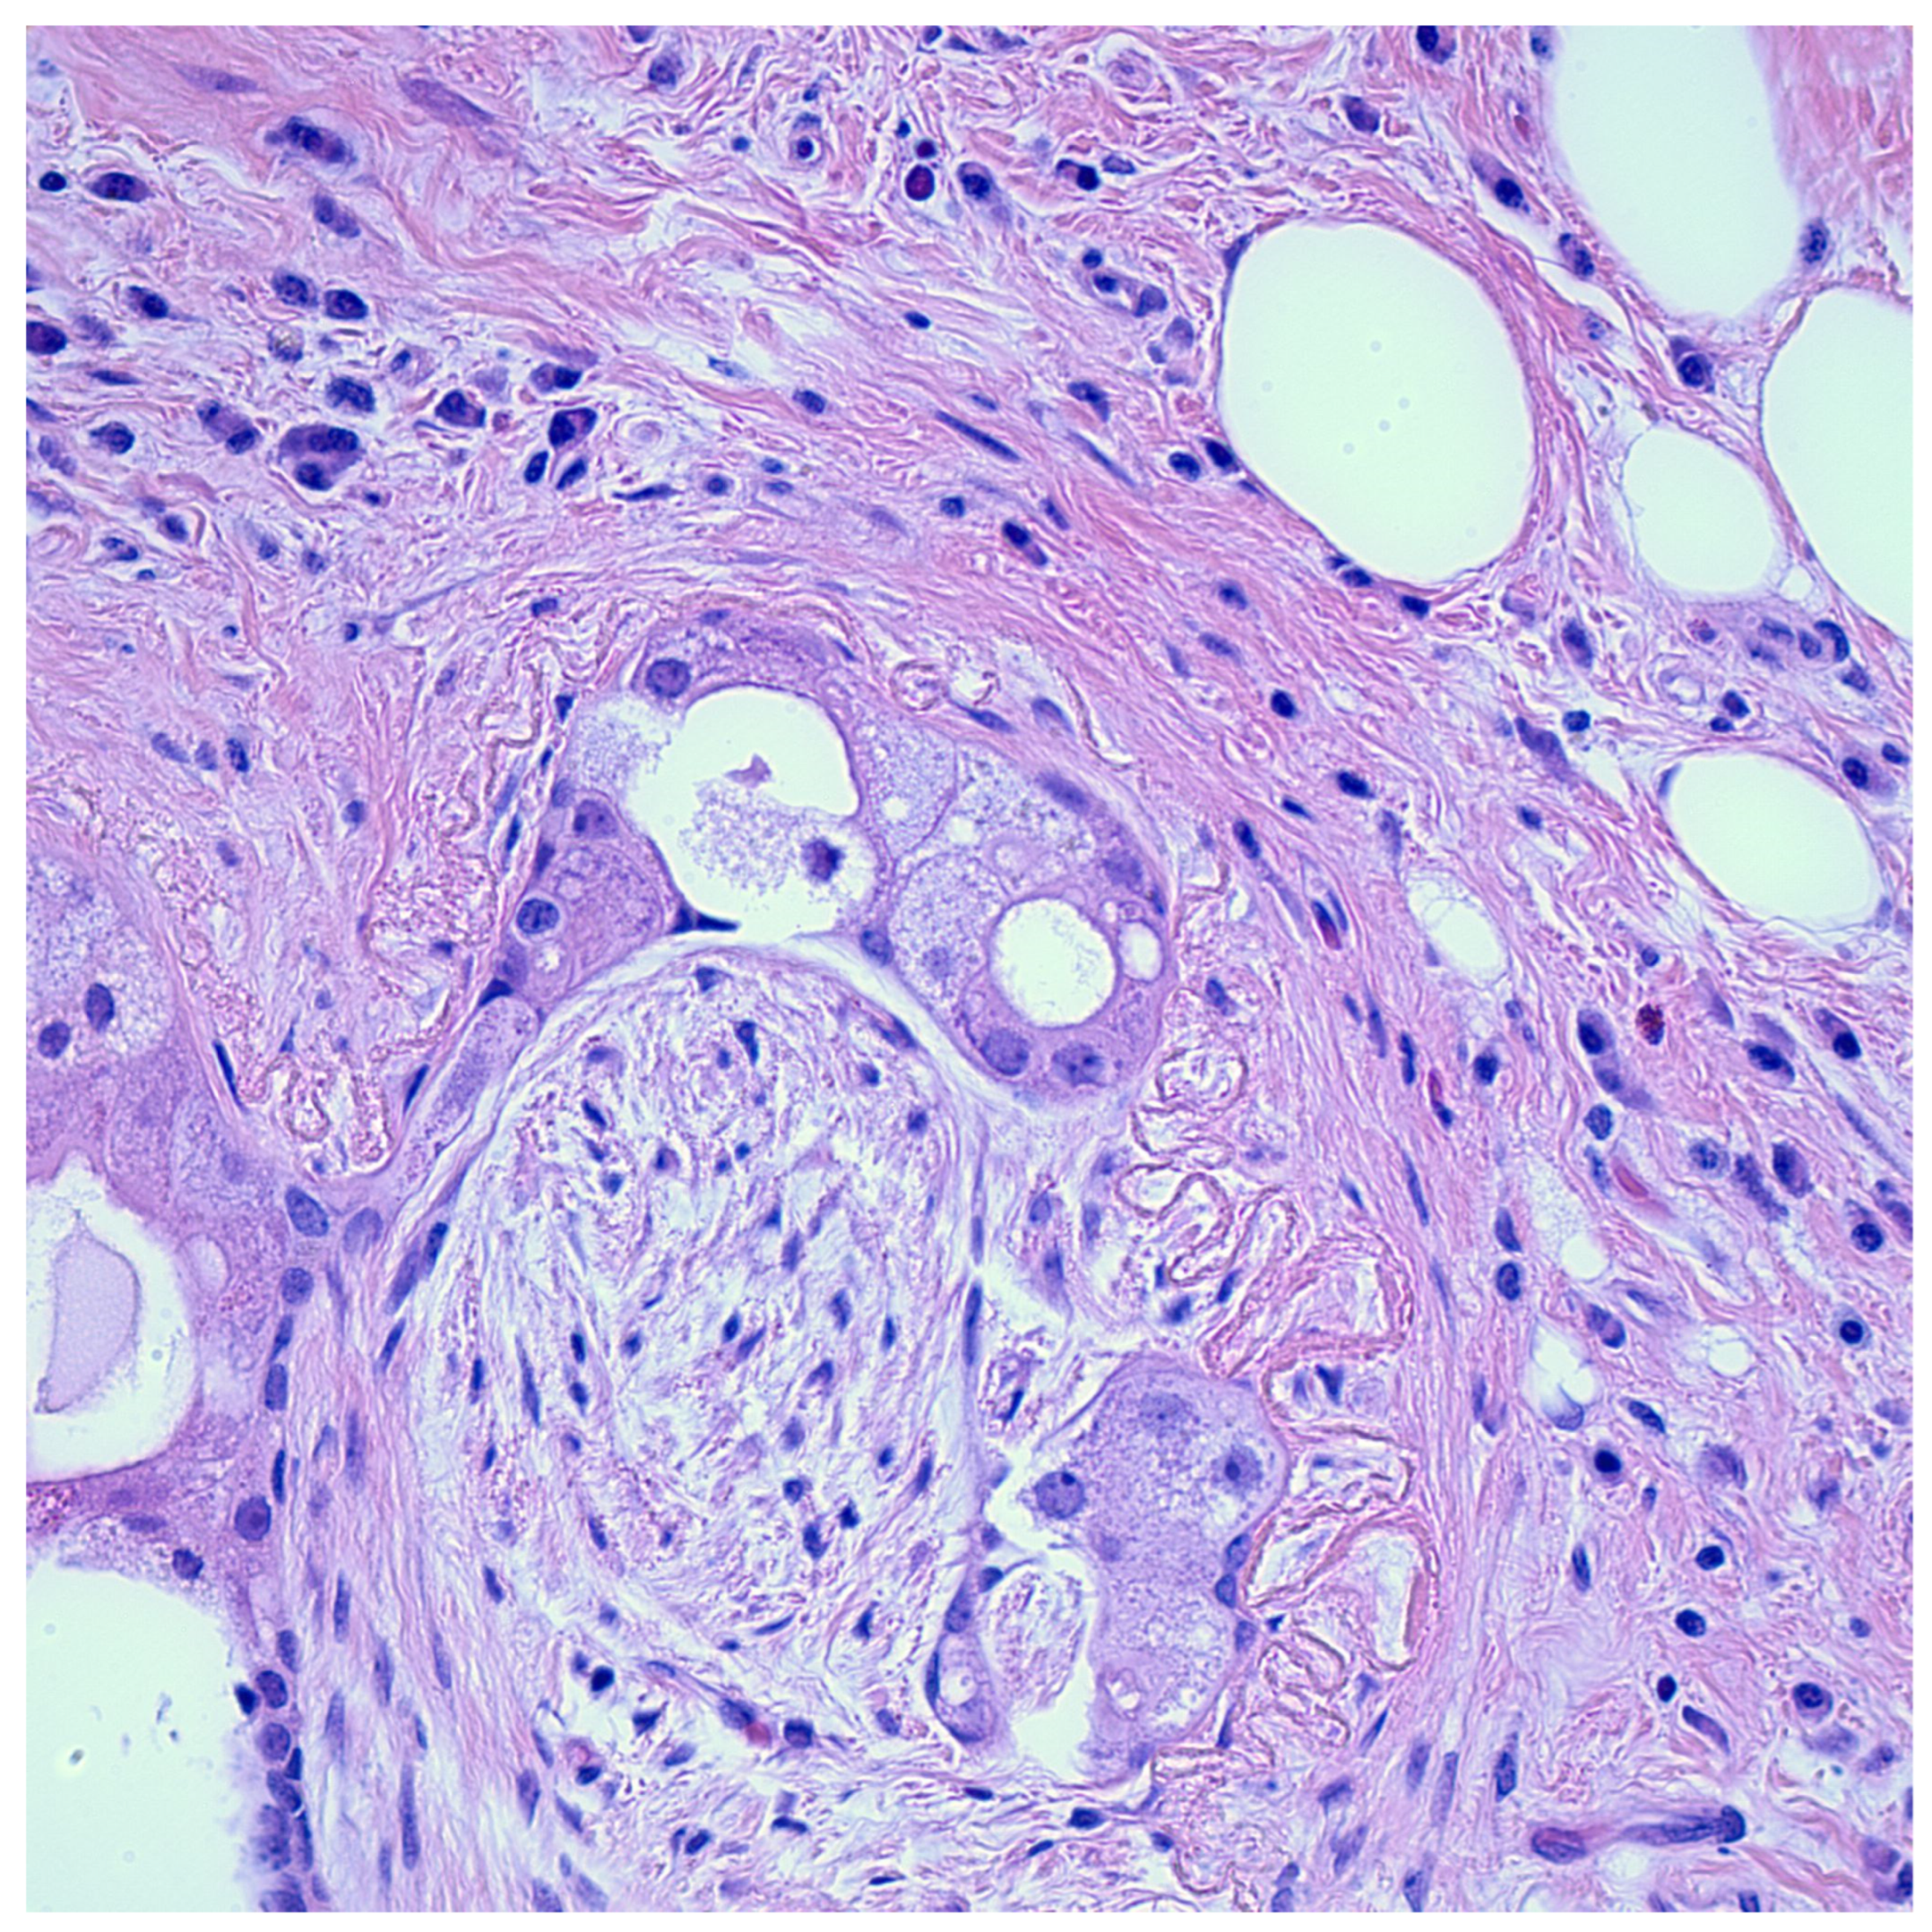

2.4. Other Pathways

4. Experimental Models of Perineural Invasion in Cancer

5. Clinical Significance of Perineural Invasion in Cancer

5.1. Perineural Invasion as a Diagnostic Marker of Malignancy in Certain Tumors

6. Benign Neoplasms Demonstrating Perineural Invasion

7. Histologic Mimics of Perineural Invasion